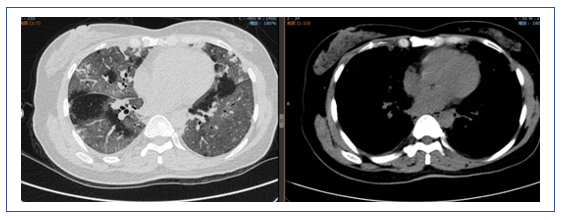

2019年1月25日,患者胸部CT显示双下肺实变较前有所吸收(图11)。

图11 2019年1月25日患者胸部CT

2019年2月1日患者胸部CT显示,上肺渗出进展(图14)。

2019年2月25日患者胸部CT示双肺病变较前吸收(图16)。